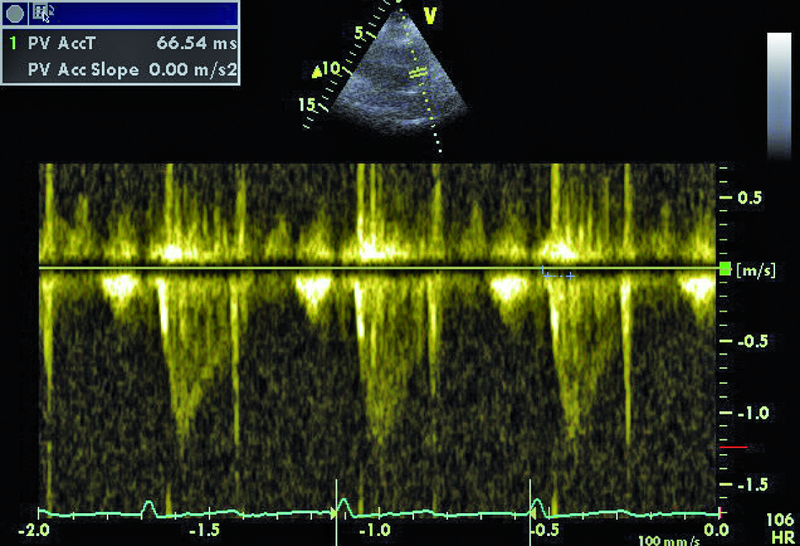

Dowodem klinicznym masywnej zatorowości płucnej był u chorej epizod omdlenia, utrzymująca się duszność, niskie ciśnienie tętnicze. Wiodącą rolę w rozpoznaniu choroby pełni tomografia komputerowa. Badanie echokardiograficzne uznawane jest za uzupełniające. Powiększenie jamy prawej komory stwierdzane w dniu hospitalizacji mówiło o możliwości istotnej dysfunkcji łożyska płucnego. Masywna zatorowość jest wskazaniem do włączenia leczenia fibrynolitycznego, zmniejszającego śmiertelność i zapobiegającego nawrotom choroby. Stan kliniczny pacjentki w wyniku zastosowanej alteplazy poprawił się. Rejestrowano zmniejszenie stężenia d-dimeru i troponiny. Czy jednak sytuacja chorej nie budzi już niepokoju? Mimo ograniczonej jakości przedstawionych rycin można dostrzec, że jama prawej komory jest przeciążona (ryc. 1, 2), a ciśnienie w łożysku tętnic płucnych szacowane z czasu akceleracji wypływu (66 ms!) jest podwyższone (ryc. 3). Im większa jest obstrukcja łożyska płucnego, tym więcej cech dysfunkcji prawej komory stwierdza się w badaniu ultradźwiękowym. Warunki obrazowania utrudniały odniesienie się do odcinkowej kurczliwości ściany wolnej i potwierdzenie lub wykluczenie objawu McConnella, czyli dysfunkcji segmentu środkowego. Ze względu na trudność w wizualizacji wsierdzia nie można było także ocenić zmiany pola powierzchni prawej komory (RV FAC). Mimo zachowanej funkcji kurczliwej prawej komory mierzonej wartością przemieszczenia pierścienia trójdzielnego (ryc. 4) uważny czytelnik z pewnością dostrzeże tkwiącą w prawej tętnicy płucnej skrzeplinę (ryc. 5, 6). Rzadko udaje się bezpośrednio uwidocznić skrzeplinę w łożysku tętnic płucnych. Kontrolne badanie TK klatki piersiowej potwierdziło obecność tzw. zatoru jeźdźca w pniu płucnym ze skrzeplinami w gałęzi prawej i gałęziach segmentalnych do płata dolnego prawego płuca. Obserwowano jedynie częściową regresję skrzeplin z tętnic płatowych i segmentalnych. Mamy więc do czynienia z nieskutecznością leczenia fibrynolitycznego (no clot resolution). Dobry stan kliniczny chorej nie wskazywał na potrzebę zastosowania leczenia chirurgicznego i embolektomii. Nie podjęto także decyzji o powtórnym leczeniu fibrynolitycznym z użyciem innego środka. Postanowiono kontynuować leczenie przeciwkrzepliwe i przeprowadzić po kilku tygodniach ponowną ocenę stanu klinicznego pacjentki i stanu łożyska tętnic płucnych. Wobec wieku chorej i licznych obciążeń internistycznych interesującą opcją leczenia (ale niestosowaną w tutejszym ośrodku) byłaby trombektomia za pomocą cewnika z miejscowym podaniem leczenia fibrynolitycznego.